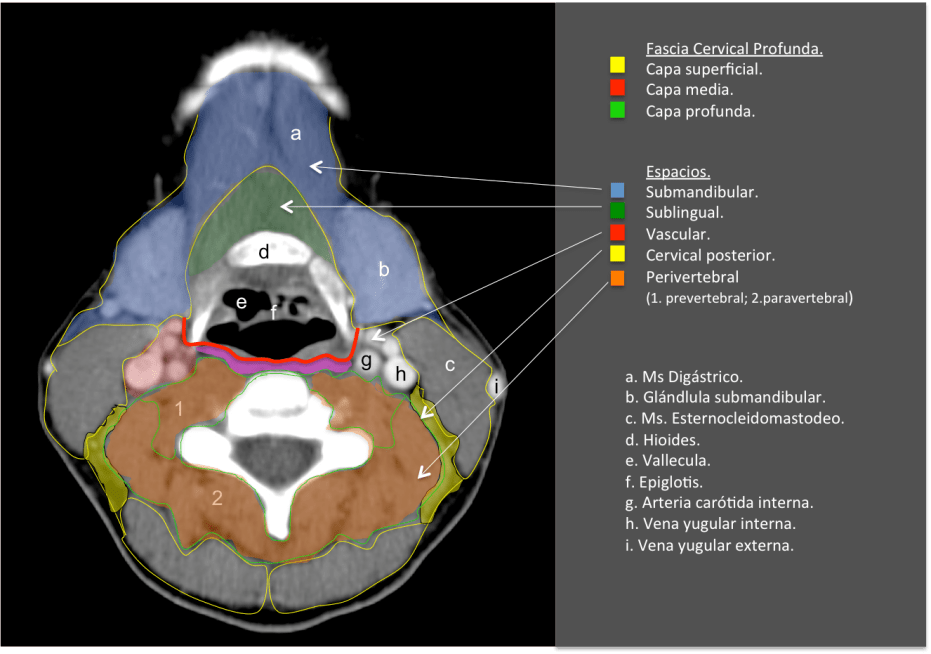

Es esencial conocer la anatomía y relaciones de los espacios cervicales y las fascias. En cuanto a la antomía superfiical, el cuello se puede dividir en:

– Cuello suprahioideo se define como el conjunto de espacios situados en la fascia profunda por encima del hueso hioides: espacio parafaríngeo, espacio de la mucosa faríngea, espacio masticador, espacio parotídeo, espacio vascular (o carotídeo), espacio retrofaríngeo y espacio perivertebral.

– Cuello infrahioideo, por debajo del hueso hiodes. Algunos de estos espacios se continúan hacia arriba (suprahioideo) y/o hacia el mediastino, incluye los espacios: visceral, cervical posterior, vascular, retrofaríngeo y perivertebral.

ESPACIO PARAFARÍNGEO.

En este espacio importante donde encontraremos mucosa y tejido linfático. Esta región puede ser el foco de origen de procesos infecciosos como faringitis, amigdalitis y/o abscesos.

Amarillo: mucosa faringea/amígdala.

Rojo: espacio vascular.

Azul: espacio masticador.

Verde: espacio parotídeo.

ESPACIO CAROTÍDEO:

Contiene la vena yugular interna y la arteria carótida, gánglios y porciones de los pares craneales IX-XII. Es importante estudiar los vasos, los cuales se rellenan fácilmente de contraste. Típicamente, la carótida se sitúa anterior y medial a la vena yugular. Una pequeña cantidad de grasa rodea estos vasos.